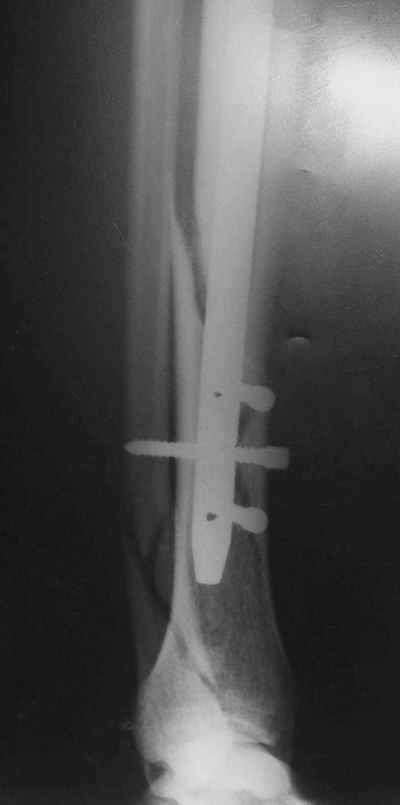

Потекли дистальные винты!

В дистальном отломке три винта( два медио-латеральных и один вентро-дорзальный).

Медио-латеральные вынты - мимо блокирующих отверстий фиксатора, вентро -

дорзальный винт - в отверстии.

Проблемы с верхним дистальным медио - латеральным винтом - он в линии перелома (

перелом косой).

То есть в дистальном отломке всего один запирающий винт. Маловато.

Если в проксимальный отломок стержень сел туго, это не мешает дистальному (широкому и короткому, раз дистальное отверстие уже на уровне перелома) быть нестабильным, особенно если он фиксирован лишь одним винтом.

Перелом спиральный, то есть низкоэнергетический, так что со сращением дело обстоит уже неплохо, лишь бы "костоеда" не развилась. Отломки выглядят уже стабилизированными костной мозолью, так что довводить винты, наверно, уже незачем. Разве что при клинической оценке подвижность еще есть - тогда можно для стабилизации наложить простейший аппарат, не опасаясь контакта его элементов с гвоздем, поскольку места в дистальном метафизе оставлено более чем достаточно.